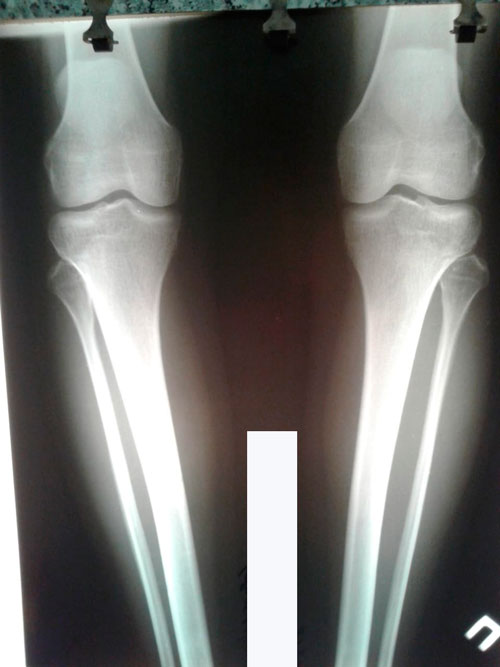

Исходник - Тараз, 35 лет.

Дата операции 04.07.2018г.